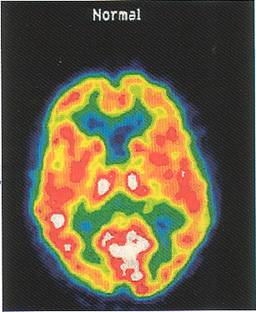

Ved scanning af hjernen aftegner man hjernens struktur, altså hvordan den ser ud. Dette gøres ved at optage snitbilleder af hjernen, enten ved hjælp af computer røntgenundersøgelse, CT-scanning, som er en standardundersøgelse ved demensudredning, MR-scanning, som er en kombineret anvendelse af magnetfelter og radiobølger, og endelig SPECT- og PET-scanning, som er en undersøgelse hvor man aftegner hvordan hjernen fungerer. De tre sidstnævnte udføres kun sjældent, da der til alle bruges meget specielt og dyrt udstyr.